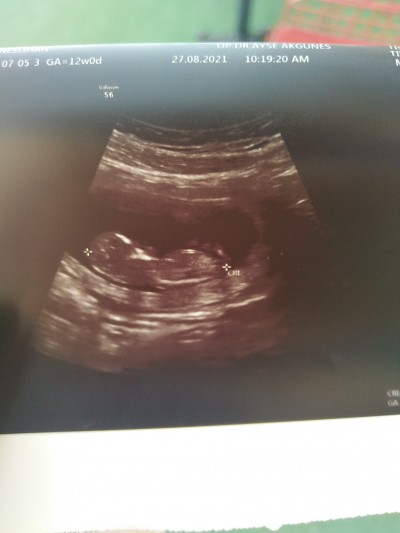

12+0ultrason görüntü doktor cok erken dedı ama cok merak edıyorum tahminimiz var ı?

Kız hissettim hayırlısı olsun canım

Eski televizyonlardaki gibi siyah beyaz şeyden ne anlayalım hissiyat dersen yanılabiliriz merak etme canim kız olan biraz gec belii ediyor kendini benim sıpa 13 haftalikken pipişini biraz göstermişti eltimin oglu 20 haftalikken gosterdi kendini hayirli sağlıklı olsun boşver merak etme doguma kadar ögrenmeyenler var :)))